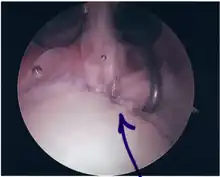

Procedure

Following inspection and determination of the extent of injury, the basic labrum repair is as follows.

- The glenoid and labrum are roughened to increase contact surface area and promote re-growth.

- Locations for the bone anchors are selected based on number and severity of tear. A severe tear involving both SLAP and Bankart lesions may require seven anchors. Simple tears may only require one.

- The glenoid is drilled for the anchor implantation.

- Anchors are inserted in the glenoid.

- The suture component of the implant is tied through the labrum and knotted such that the labrum is in tight contact with the glenoid surface.